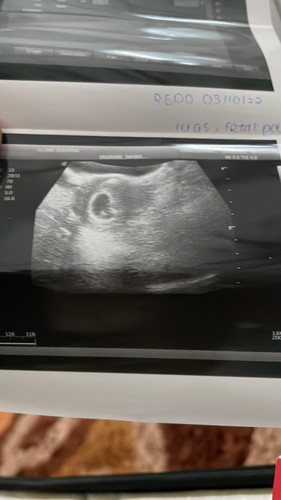

Alhamdulillah dah scan tadi and lari kiraan 3minggu.. so skrng saya bru 5minggu 5hari..kalau ikut tarikh period tu jdi 8minggu..jadi takut sangat tadi berdebar semua ada huhu but alhamdulillah dah nampak kantung and ada fetal pole😭 nangis juga ler terharu doc cakap rezeki saya lekat 2hari sblm tarikh period..alhamdulillah syukur doakan saya semoga dapat menjaga sehingga bersalin 9b10h amanah allah utk keluarga kecil saya..aminn #firstbaby #5week5day